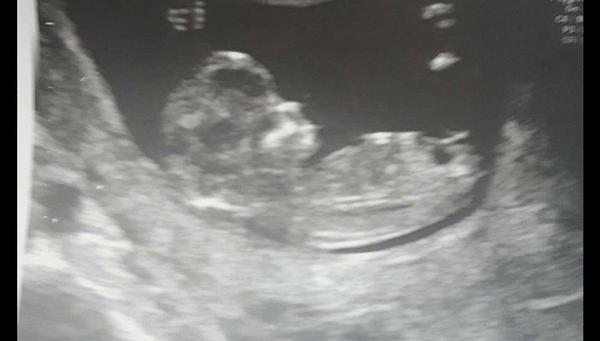

Ahoj holky, čekáme s přítelem první miminko.... Moc se na něj těšíme. Pohlaví nám pan doktor neurčí, musí počkat na další screening ve druhém trimestru. Ale prakticky všichni z rodiny vidí na fotkách z ultrazvuku kluka, co myslíte, může to být kluk??

Podle prvni cernobile fotky to vypada na holcicku.

taky tipuju holčičku